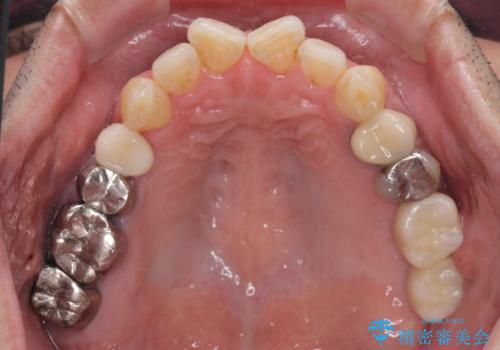

左上の奥歯は2本抜歯が必要であったため、治療期間中は右側に負担がかかり、頻繁に仮歯が壊れてしまいました。

左上に仮歯が装着されたからは咬み合わせが安定し、スムーズに治療を進めることができました。